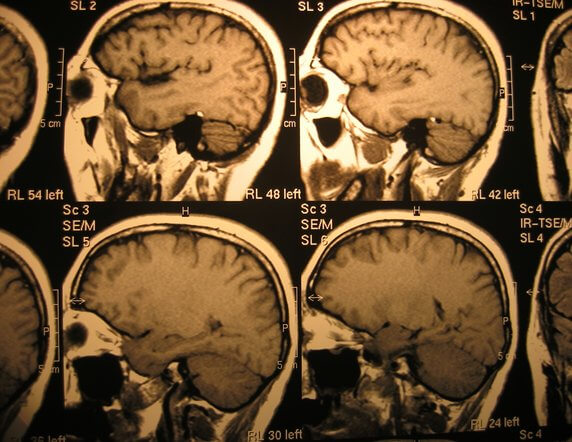

No momento do DHS, uma configuração de anel alvo aparece em um revezamento cerebral específico, dependendo da natureza exata do conflito, e começa a desencadear uma seqüência de eventos no corpo físico.

O que ocorre fisiologicamente depende da área do cérebro em que esse DHS causou seu impacto. Estes anéis alvo são visíveis em alguns casos até mesmo para o olho destreinado e foram originalmente pensados como “artefatos” nos TCs do cérebro.